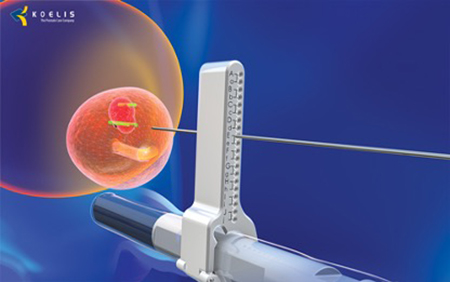

Το τελευταίας τεχνολογίας σύστημα πλοήγησης Koelis TRINITY PERINE σε συνδυασμό με την άρτια επιστημονική κατάρτιση και εξειδίκευση του ιατρικού μας προσωπικού του τμήματος βιοψίας προστάτη, καθιστούν τον όμιλο ΙΑΤΡΟΠΟΛΙΣ τον μοναδικό στην Ελλάδα, που έχει την δυνατότητα βιοψίας ελαστικής σύντηξης μέσω διαπερινεϊκής προσπέλασης, υπό τοπική αναισθησία.

- Ελαχιστοποιείται ο κίνδυνος μόλυνσης (η βελόνα δεν περνά πλέον από το ορθό)

- Πραγματοποιείται υπό τοπική αναισθησία.

- Ελάχιστη δυσφορία για τον ασθενή κατά τη διάρκεια της διαδικασίας.

- Επιστροφή του εξεταζομένου στις καθημερινές του δραστηριότητες μετά το πέρας της βιοψίας.

Ακολουθούν Εικόνες

TRANSPERINEAL BIOPSY